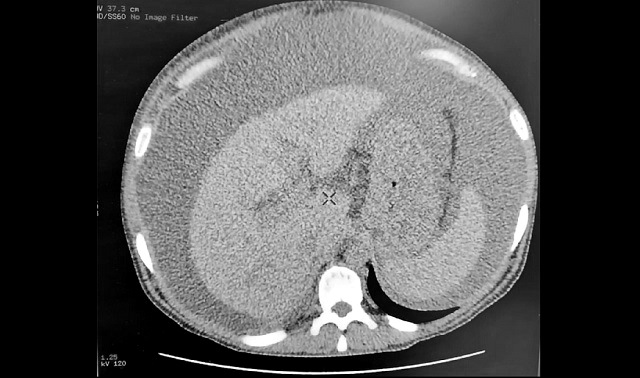

32-летний житель Набережных Челнов заработал себе цирроз печени, злоупотребляя спиртными напитками. Вследствие чего в его животе скопилось 10 литров свободной жидкости, передает пресс-служба Горздрава автограда.

По словам завотделением лучевой диагностики горбольницы №5 Рузаны Миннехановой, практически все органы пациента необратимо повреждены, особенно печень. Состояние пациента удалось стабилизировать, но о полном выздоровлении речь не идет.

Фото: телеграм-канал «Горздрав Челны»